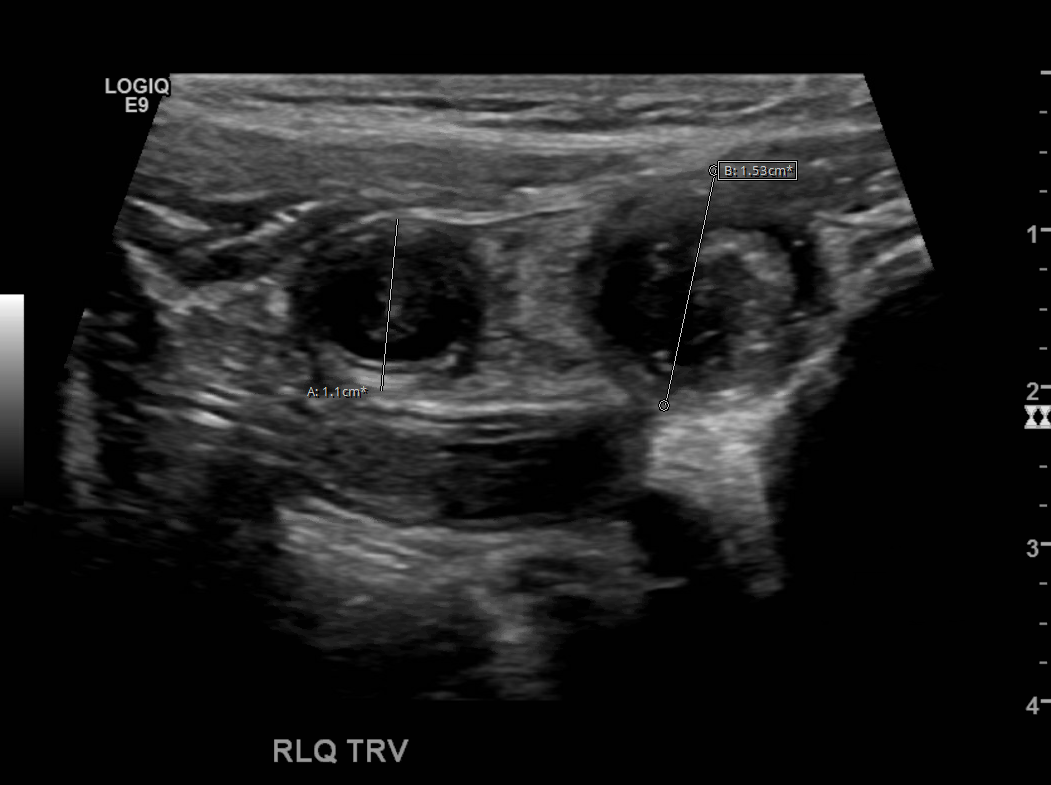

Appendicitis 15

Appendicitis 16

Hyperemia, echogenic fat and appendicolith